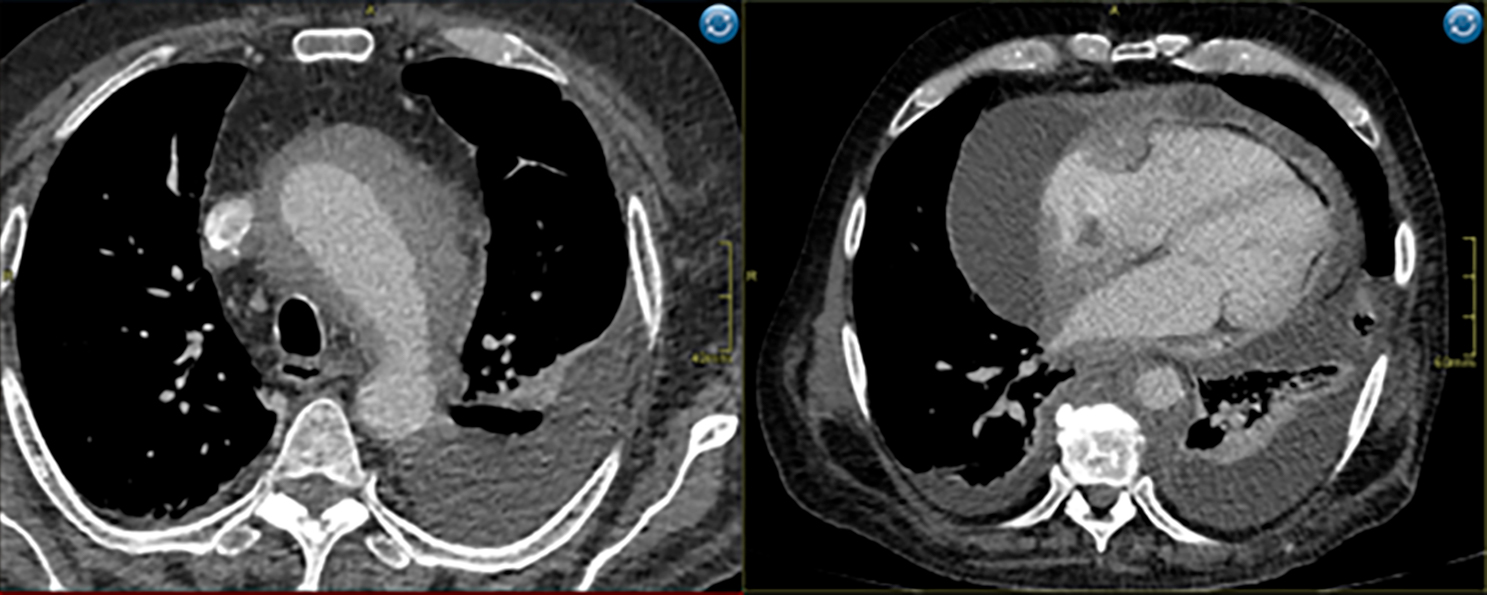

Компьютерная томография органов грудной клетки (КТ ОГК Плевральный выпот слева составляет 1180 мл, а в полости перикарда обнаружено 550 мл частично осумкованной жидкости вдоль правого предсердия. Диффузное уплотнение клетчатки вокруг восходящей части грудной аорты, сливающейся с аортой при нативном исследовании. Медиастинальные и аксиллярные лимфатические узлы не увеличены и четко не дифференцируются.

Рис. 1. КТ ОГК Поражение аорты, перикарда и периваскулярные муфты, 2023 год

КТ: Отмечается наличие муфтообразного утолщения ткани вокруг грудной аорты, умеренно накапливающей контрастное вещество, с максимальной выраженностью вокруг дуги аорты (рисунок 1а). Аналогичные периваскулярные муфты отмечаются вокруг коронарных артерий, преимущественно вокруг правой коронарной артерии (наружный диаметр муфты — 25 мм, просвет артерии — 3-5,5 мм) — рисунок 1б.

В нижней трети верхней полой вены (ВПВ) выявлено пристеночное утолщение протяженностью до 7,5 см и поперечным размером до 20 мм, которое распространяется в правое предсердие и умеренно накапливает контрастное вещество в венозную фазу. Наружный край ткани, пролабирующий в просвет, аваскулярен, возможно, покрыт тромботическими массами. В правом предсердии выявлен флотирующий фрагмент длиной около 27 мм и толщиной 10-12 мм.

Перикардиальные листки неравномерно утолщены (рисунок 1б), что, вероятно, обусловлено узловатой инфильтрацией. Между листками содержится небольшое количество жидкости, разделенной перегородками.

Кнаружи от правого предсердия наблюдается осумкованное жидкостное скопление линзообразной формы, толщиной до 5,8 см и объемом 480 мл (рисунок 1б)

Рис. 4. Циркулярная инфильтрация вокруг восходящего отдела аорты (аорта окружена муфтообразной тканью) — синдром «обложенной» аорты, coated aorta sign. Слева 2025 год, справа 2023 год.

Сагиттальная проекция.